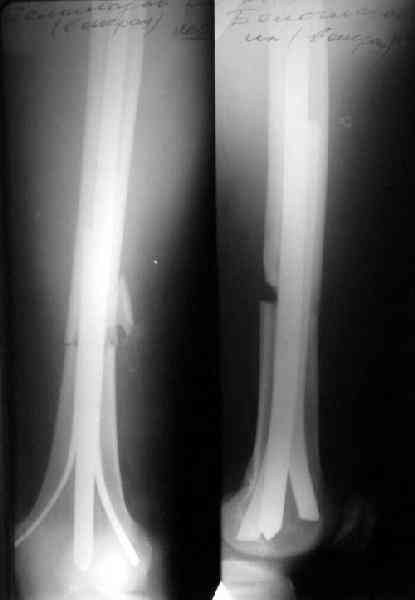

Еще вариант - ввести традиционный 4-гранный, кюнчеровский, или какой есть гвоздь помощнее (можно и антеградно, но хоть даже и открыто ретроградно, традиционно со стороны перелома), а со стороны надмыщелков заклинить его одним или двумя плоскими стержнями. Пример в приложении.